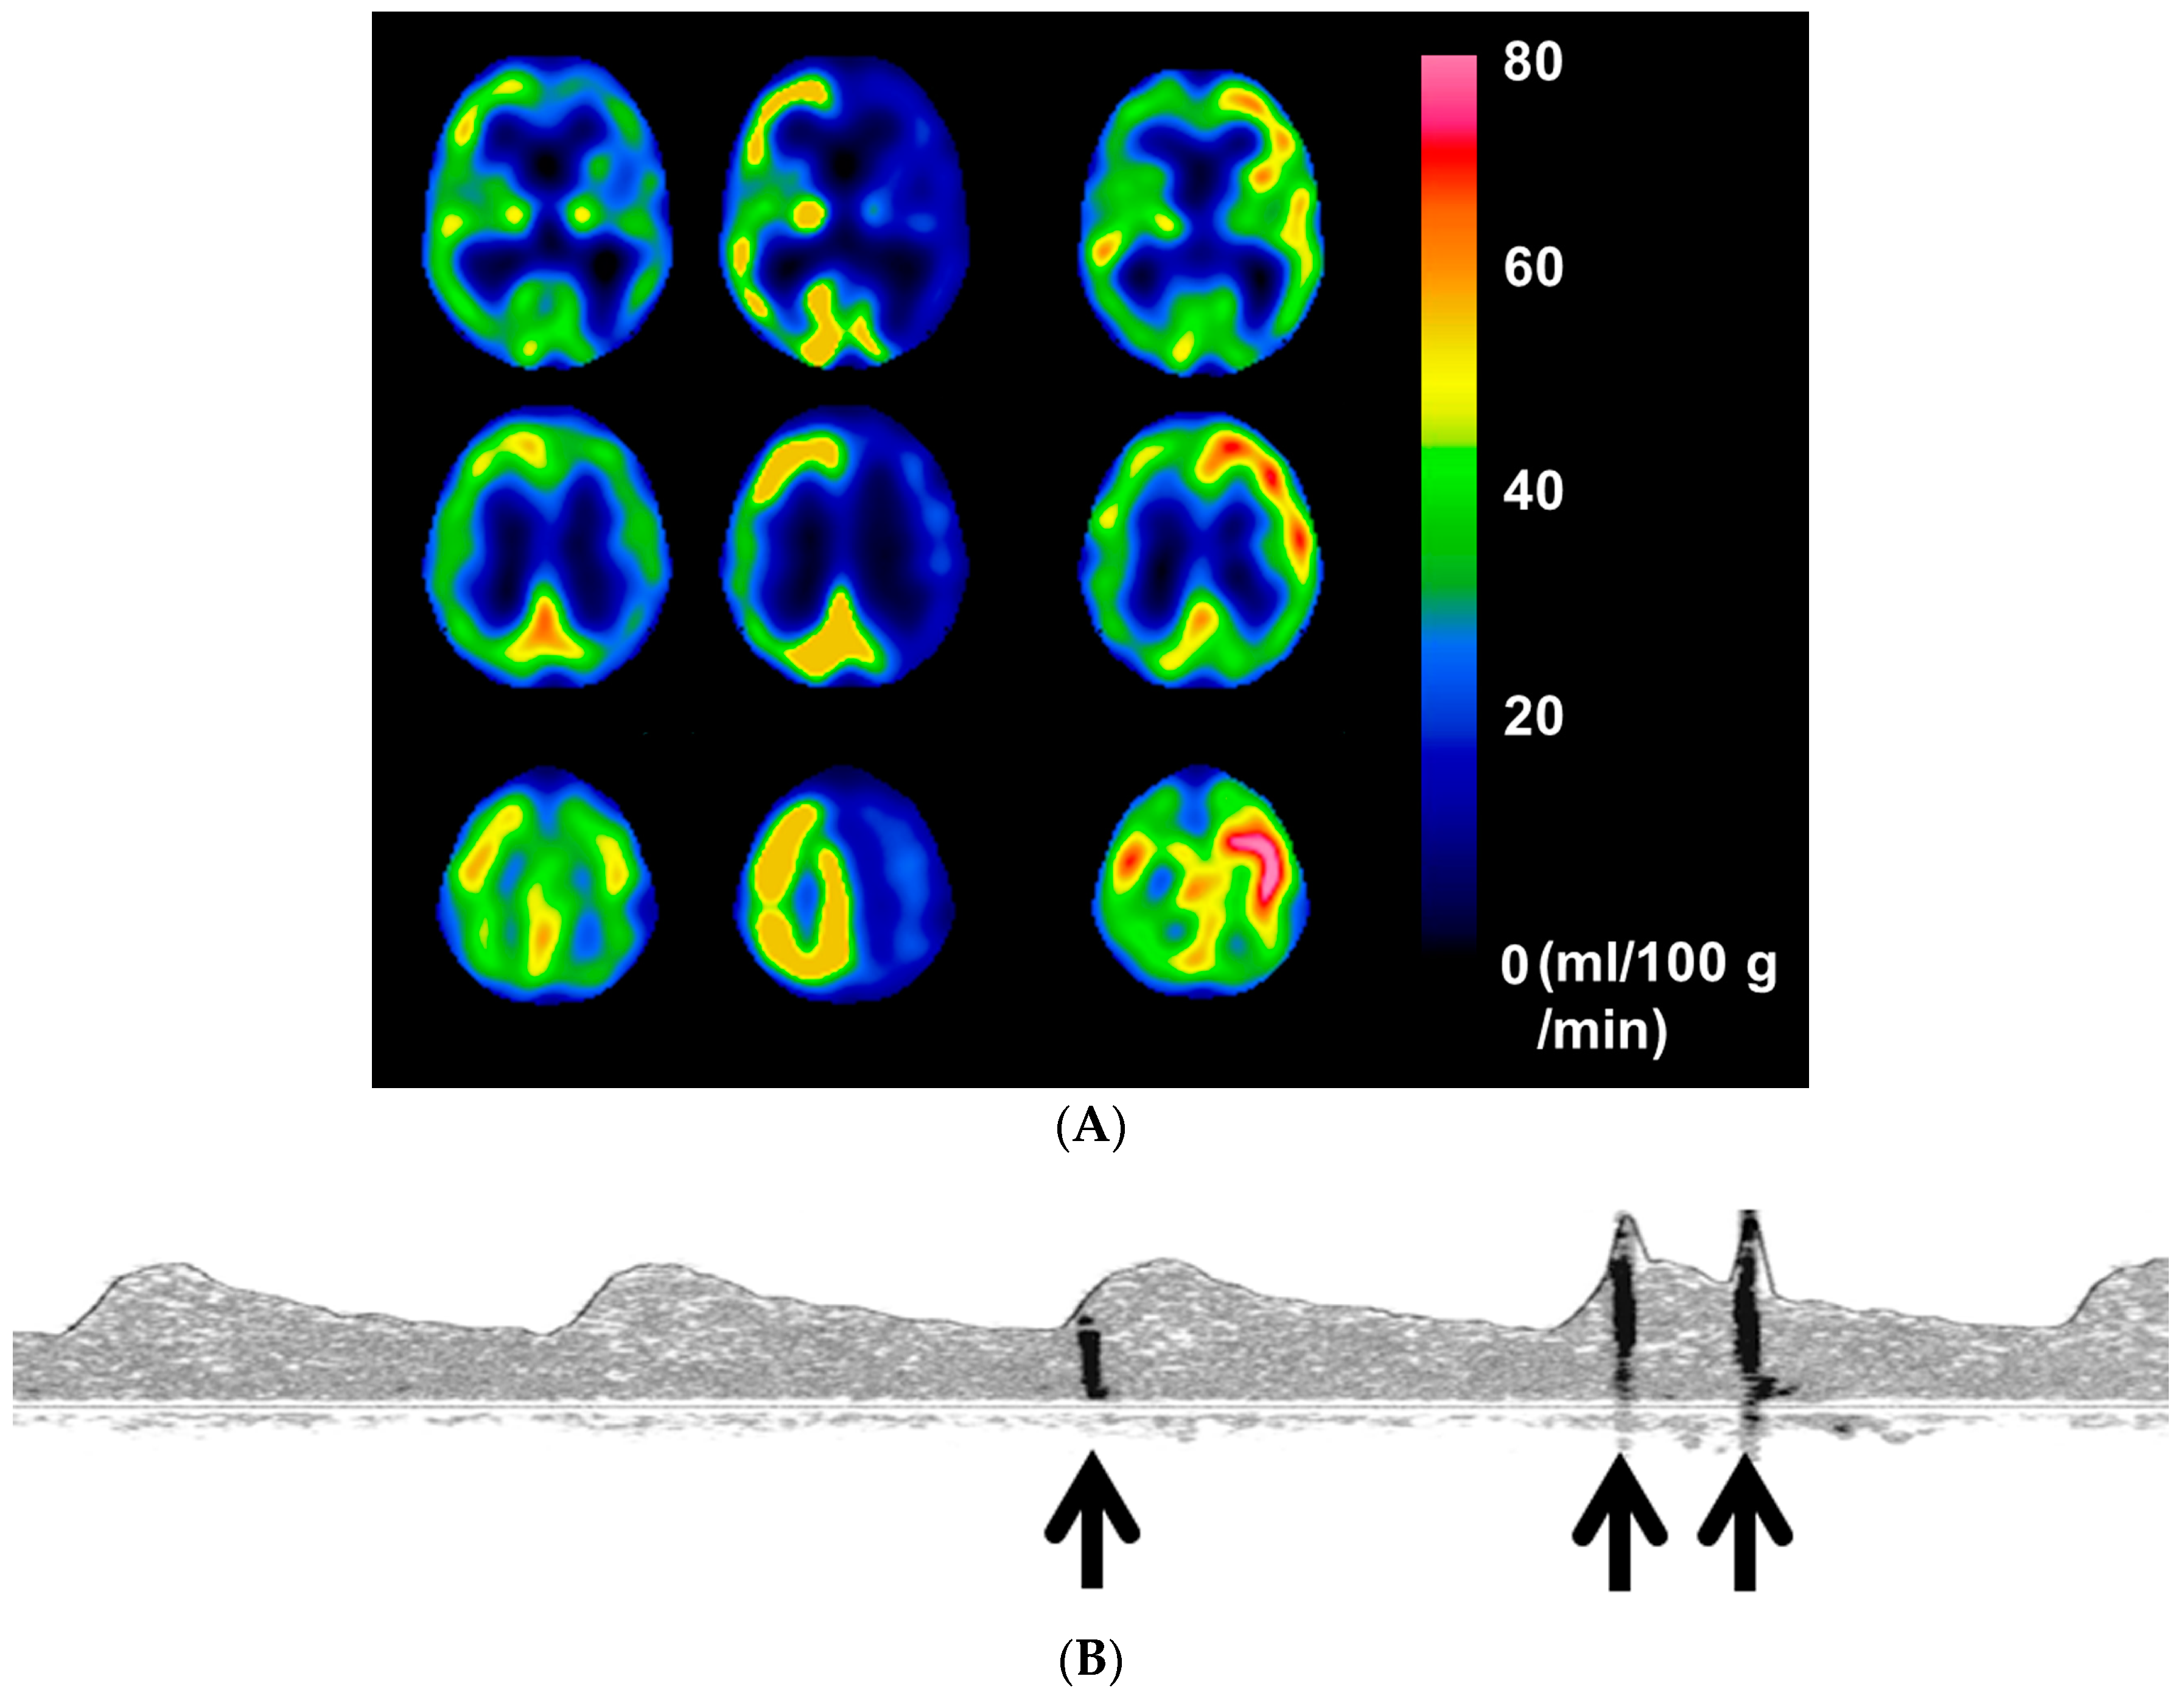

2.5. Case Presentation